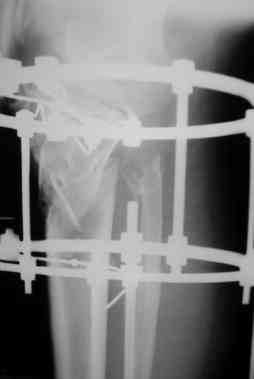

Р-граммы за март и апрель